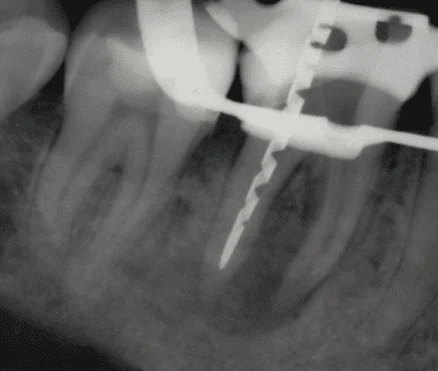

Endodontics Applications

The LiteTouch Er:YAG laser has demonstrated high effectiveness in eliminating bacterial biofilm and smear layer throughout the root canal system, including anatomically complex areas such as dentinal tubules, lateral canals, isthmuses, ramifications, and the apical region. This enhances the penetration of the irrigant and improves the prognosis of both. Beyond the Laser-Activated Irrigation, the LiteTouch can also be applied in surgical procedures such as apicectomy. It is suitable for all stages of the surgery, including flap release, bone ablation, granulation tissue removal, and apical resection. This minimally invasive approach ensures thorough decontamination of the surgical site and contributes to favorable healing (Figure 4).